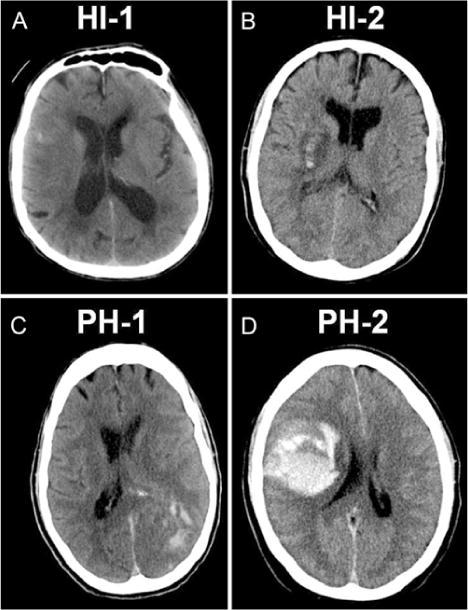

v 根据影像学上有无血肿占位效应,又将HT分为脑实质内出血(parenchymal hematoma,PH)和出血性梗死(hemorrhage infarction,HI)。表2是根据影像学特点(部位和形态),不同研究对AIS后出血转化定义的影像学分型,其中ECASS分型比较常用,图1是ECASS出血分型。

HI-1:沿梗死灶边缘的小点状出血;

HI-2:梗死灶内片状无占位效应出血或多个融合的点状出血;

PH-1:血肿<梗死面积的30%并有轻度占位效应;

PH-2:血肿>梗死面积的30%并有明显占位效应的出血或远离梗死灶的出血。

A~B为渗出型出血;C~D为血肿型出血。